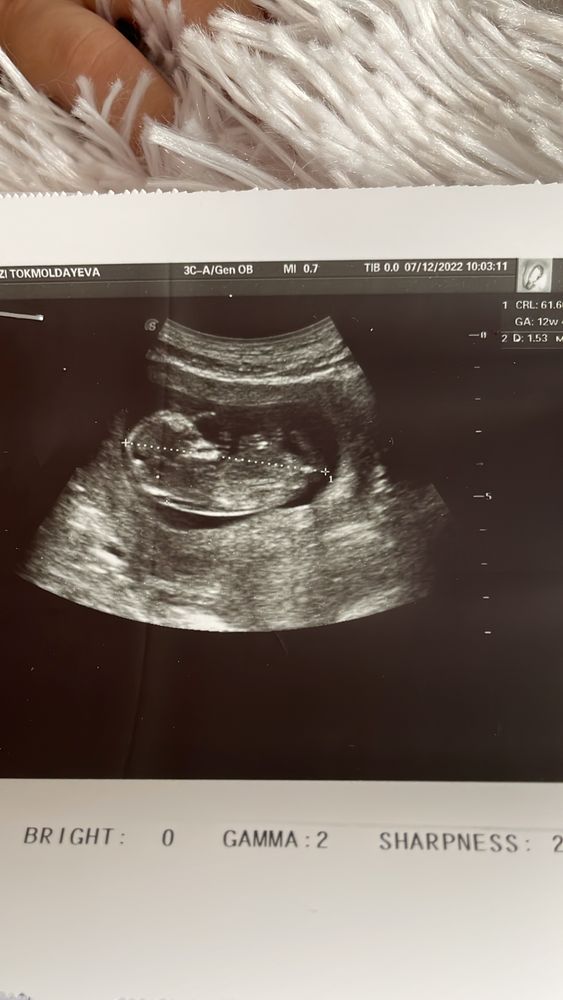

А узи делали? По узи все хорошо? Носовая кость в норме?

Алиса , Изображение

Изображение Аида ,

Аида , по узи у вас все в норме, не переживайте раньше времени, этот анализ крови ещё ничего не значит, этот анализ мало изучен, врачи больше делают акцент на узи, если сомневаетесь, то лучше нипт сделать в частной клинике, но не соглашайтесь на прокол, опасная процедура, рисков много